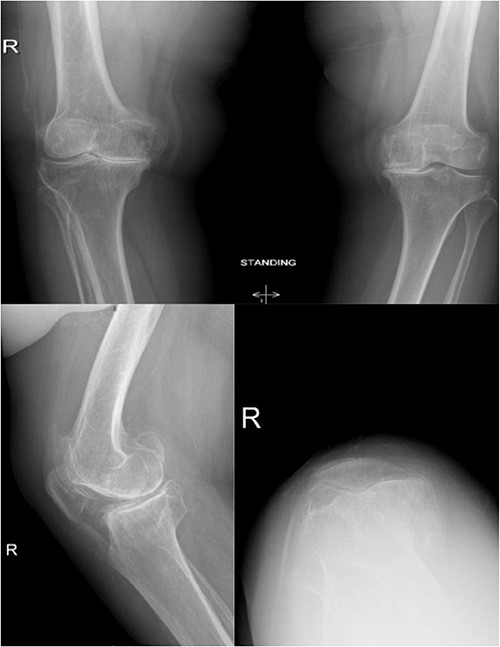

A 66-year-old woman with a history of right femoral shaft fracture, which was managed conservatively and resulted in malunion with right varus knee deformity. At the age of 54 years, she was diagnosed with osteoarthritis, and conservative treatment options, including weight reduction, non-steroidal anti-inflammatory medications, physiotherapy and intra-articular steroid injections, had been exhausted. Knee pain continued to worsen over the years, with negligible improvement in her symptoms. On physical examination, there was obvious varus deformity of the right knee, and significant restriction in the range of motion from full extension to 90° flexion. X-rays were requested, which revealed severe tri-compartmental knee osteoarthritis, a 3 cm medial shift of the right lower-limb mechanical axis, and 80° anatomical lateral distal femoral angle (aLDFA) and 96° mechanical lateral distal femoral angle (mLDFA) (Figs 1 and 2). The findings were discussed with the patient, who agreed to proceed with TKA. Given the complexity of this case with the femur deformity, the CORI Smith & Nephew surgical arthroplasty system was recommended as the surgical option that was suited to the patient’s specific bony anatomy and appropriate positioning of the components.

Preoperative anteroposterior standing bilateral lower extremity radiographs displaying long leg alignment and the right femur Varus deformity.

Preoperative anteroposterior, lateral and sunrise radiograph views displaying tri-compartmental osteoarthritis.